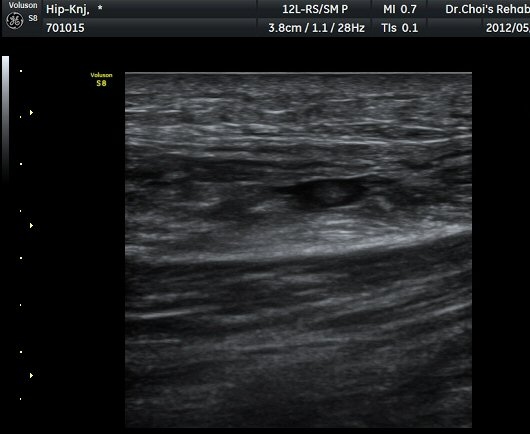

ŽÃËÀÚ¸¦ ¾Æ·¡·Î À̵¿ÇÏ´Ï ´ëÅðÁ÷±Ù³»¿¡ Àú¿¡ÄÚ º¯º¯ÀÌ °üÂûµÈ´Ù(±×¸² 2, 3).

´ëÅðÁ÷±Ù Á¾´Ü¸é°Ë»ç¿¡¼­ ±ÙÀ°³»¿¡ ¼±»óÀÇ Àú¿¡ÄÚ °¢±ØÀÌ °üÂûµÈ´Ù(±×¸² 4, 5).